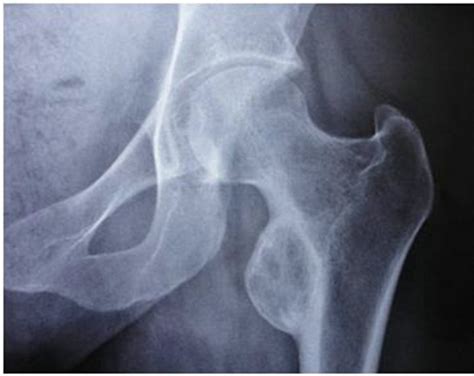

Intertrochanteric fracture of the femur | Image ...

Intertrochanteric fracture of the femur | Image ... from images.radiopaedia.org

It's around 18 inches (45 long), i.e., about quarter of the… the upper end contains the head, neck, and lesser and greater trochanter. The shaft of the femur is gradually convex anteriorly with maximum. All of the body's weight is supported by the femurs during many activities, such as running, jumping just medial and distal to the greater trochanter is a smaller projection known as the lesser trochanter. Lesser trochanter of femur, lesser trochanters, lesser trochanter. Small trochanter) is a conical eminence, which varies in size in different subjects; The severe displaced lesser trochanter may increase postoperative complications and postoperative pain in the treatment of unstable trochanteric femur fractures. The lesser trochanter is the smaller posterior projecting protuberance at the medial base of the femoral neck. The lesser trochanter is a small protuberance of bone that projects from the posterior aspect of the femur, inferomedially at the base of the femoral neck.